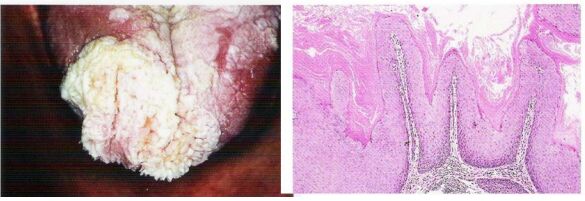

41. 男性 58 歲患者, 臨床檢查舌內出現白色棘狀凸起外觀似白花菜 3 年。請問其診斷結果為何(A) Squamous cell carcinoma(B) Adenocarcinoma(C) Small cell carcinoma(D) Verrucaous carcinoma